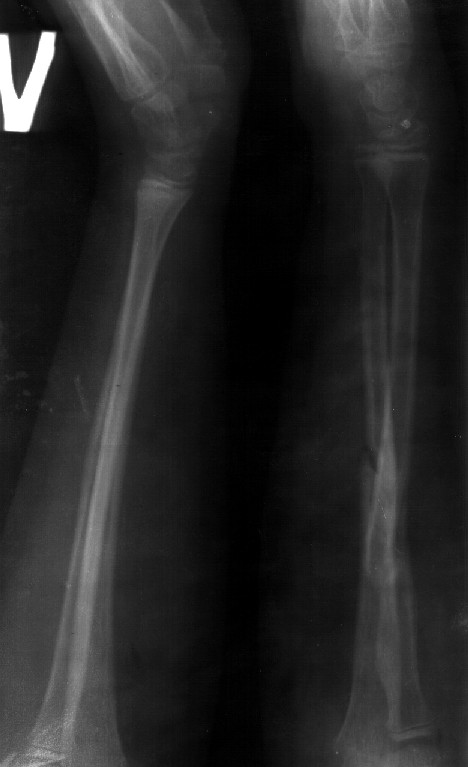

Сделал симметричные снимки с максимальной супинацией и пронацией при согнутом предплечье в 90 град. Объем ротационных движений 90-100 град.

СМ> Сделал симметричные снимки с максимальной супинацией и пронацией при

СМ> согнутом предплечье в 90 град. Объем ротационных движений 90-100 град.

Снимок один сделан с супинацией, второй - оба предплечья в одинаково нейтральном положении. то есть по этим снимкам объем ротационных движений не оценить. Снимко в двух проекциях лучше и делать в среднем положении между пронацией и супинацией, то есть обе проекции в однм и том же положении, когда линия, проходящая через шиловидные отростки, идет в плоскости головки. Прошу прощения за усложнение простых вещей.